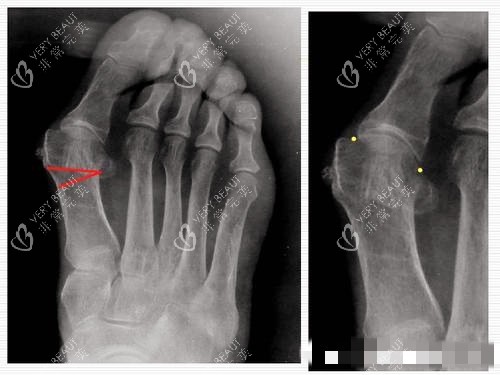

术后***0天,我开始尝试穿前足减压鞋行走。温医师在微信上提醒:“每天走20分钟,循序渐进,别急着跳操。”当我说出“走起来比术前轻松多了”时,他回复了一个笑脸表情。术后第3周,我进行了头一次复查,X光片显示截骨端已初步愈合,温医师说:“可以试着穿软底运动鞋,但别穿高跟鞋。”

现在,术后1个月,我的足部已经完全“定型”:正面看,大脚趾与第二脚趾呈15度正常夹角;侧面看,足弓线条流畅,穿运动鞋时足底压力分布均匀;仰头看,足部外观自然,切口痕迹几乎不可见。让我满意的是手感——摸上去软软的,像自己的肉,用力按压也不会有“硬块感”。

大脚骨X光片图片